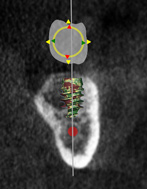

(3.) CBCT scan of tooth No. 12, exhibiting a retained root that previously received root canal treatment.

Figure 3

After a CBCT scan (Figure 3) and a digital impression were obtained for diagnosis and treatment planning, the DICOM file from the CBCT scan and the STL file from the digital impression were merged in a treatment planning software application for evaluation. A virtual crown was then created to facilitate a restoration-driven approach. The vital structures and osseous anatomy were identified, and the implant position was planned virtually (Figure 4 and Figure 5).